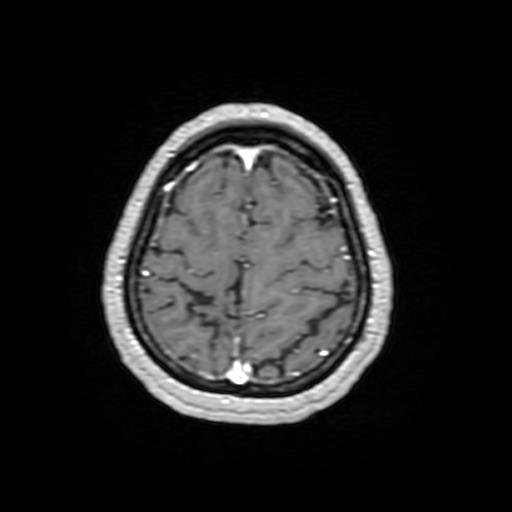

Hình 2: Hình ảnh chụp cộng hưởng từ sọ não có tiêm thuốc đối quang từ: hình ảnh tổn thương thuỳ đỉnh phải – Theo dõi tổn thương cũ, thoái hoá myelin (không có tổn thương nghi ngờ thứ phát)